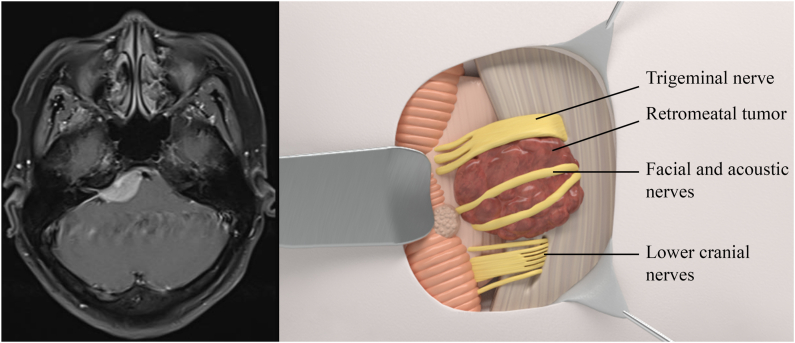

Fig. 1.

Left: MRI scan of retrometal meningioma. Right: Relationship of cranial nerves to retrometal meningioma using 3D illustration.

Retromeatal meningiomas (Fig. 1) are relatively safer to resection than other groups of CPA meningiomas thanks to the tumor being superficial, involving mostly the cerebellum. Cranial nerves are pushed anteriorly and inferiorly. More specifically, the VII/VIII complexes are pushed anteriorly (85 %) or inferiorly (15 %). The lower cranial nerves IX, X, XI, and PICA are pushed inferiorly. In addition, the site of dural attachment is between the IAM and the sigmoid sinus. As a result, devascularization and debulking were more favorable.